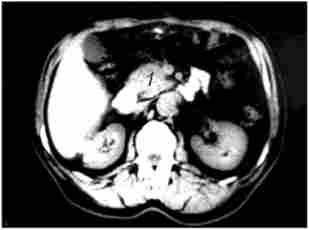

Суттєве значення в діагностиці пухлин ПЖ має Комп'ютерна томографія. Основні ознаки, що дозволяють запідозрити рак ПЖ при комп'ютерної томографії: збільшення розмірів залози на локальній ділянці, горбисті контури ПЖ в цій області, наявність пухлиноподібних гіподенсного вузла, пухлинна інвазія періпанкреатічної клітковини. Розширення ДПП при КТ діагностується набагато рідше, ніж при УЗД, що пов'язано з великою товщиною зрізів при КТ (5-8 мм). Діагностична точність КТ становить 72-91%. Роздільна здатність КТ в основному близька до такого при УЗД, хоча метод має дещо більшою інформативністю у встановленні поширення раку ПЖ на навколишні органи і структури, в виявленні регіонарних метастазів (рис. 21.2 і 21.3).

Мал. 21.2. Комп'ютерна томографія. Рак головки підшлункової залози:

1 - гіподенсная горбиста пухлина головки підшлункової залози 4 х 5 см